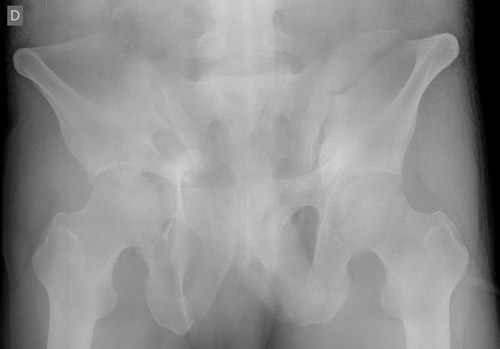

Pre-op X-Rays after applying correct amount of binder compression

Pre-op X-Rays